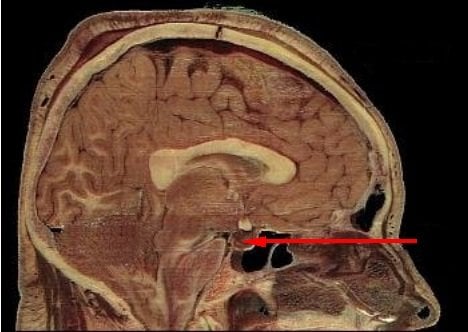

This image shows the location of the pituitary gland in the human brain.

FeaturedNeurology

·September 26, 2013·4 min read

Soldiers With Blast Injuries Suffer Pituitary Hormone Problems

Soldiers who suffered TBI as a result of an IED blast are more likely to have pituitary hormone problems than patients with TBI caused by accidents, a new study suggests.